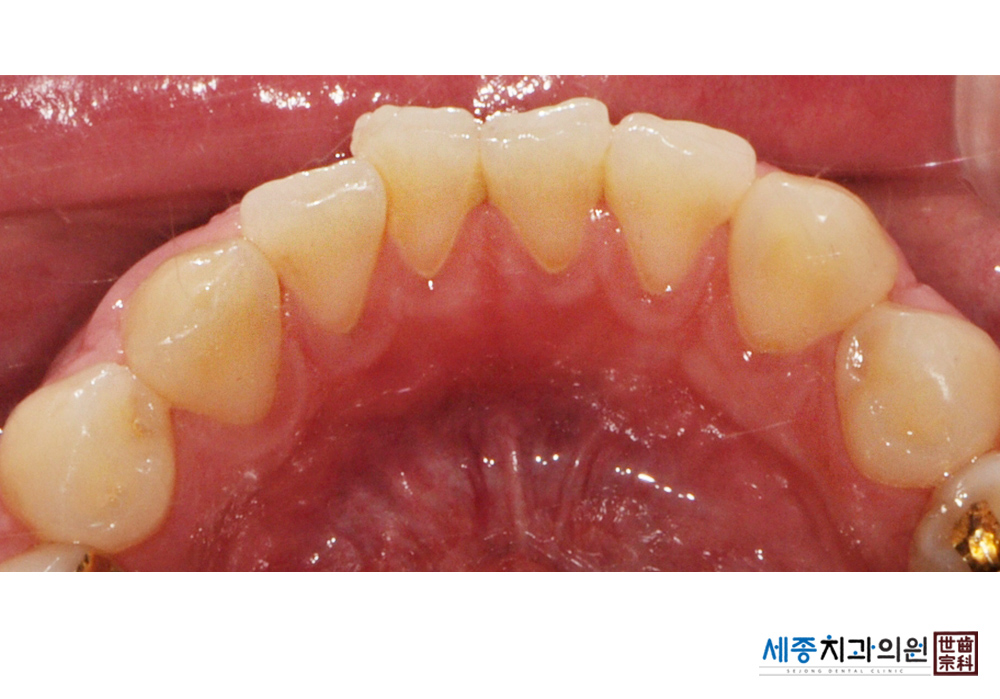

[스케일링] 치주질환 예방 스케일링

치료전 : 2022-02-16

치료후 : 2022-02-16

가글마취&저주파 스켈러를 사용한 스케일링